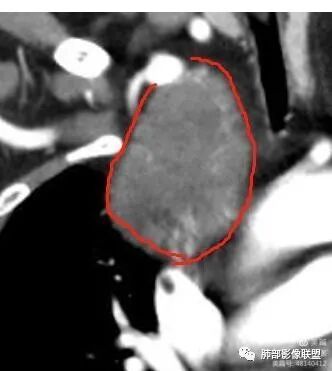

1. 右上胸廓入口区类椭圆形块影,边界清楚光整,纵向“嵌顿”于颈根部及上纵隔,向上推移右锁骨下动静脉,向外下方推移上肺胸膜及肺组织(肺血管、支气管),向前推移上腔静脉,界限清楚。

2. 块影不均匀轻度强化,可见较均匀实性区及液性密度区,未见积气、囊壁样结构、钙化或脂肪密度。可疑部分肋间动脉分支进入。

3.而“A/B”区密度特点以及上下径较大更支持神经鞘瘤,尽管这不属于好发部位。